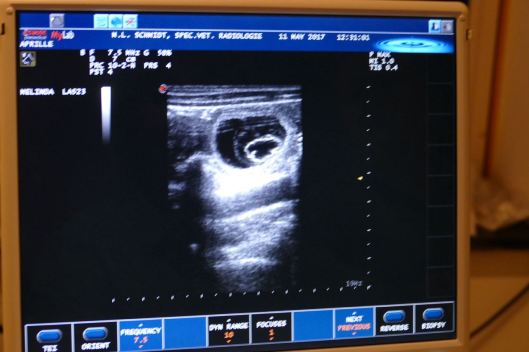

Marianne had voor vandaag een afspraak gemaakt om een echo te laten maken van Aprille’s buik. Dit is voor ons de vierde generatie die bij Paula in het liggootje belandde, voor hopelijk heuglijk nieuws; Jewel lag hier in 2008, haar dochter Hinde in 2011 en Hinde’s dochter Megan in 2014. Aprille liet het allemaal heel rustig over zich heen komen….

Paula zag Aprille’s tepels en wist het al zeker: die is zwanger! Vervolgens bracht ze een aantal Salty Sand’s D-tjes haarscherp in beeld, met duidelijk kloppende hartjes. Het blijft prachtig om te zien, ook al weten we ondertussen wel hoe een vruchtje van 4 weken eruit ziet. Dat waar je met elkaar op hoopt, wordt opeens gewoon zichtbaar….

Paula is altijd oprecht blij wanneer de zwangerschap een feit blijkt te zijn en ze deze zo mooi in beeld kan brengen.